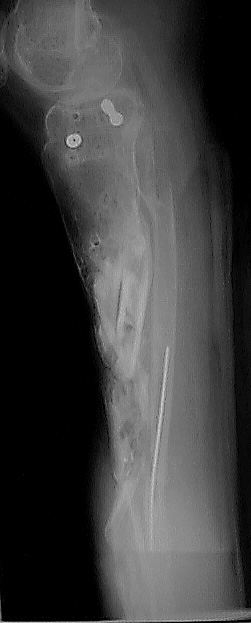

Case 1

Fifteen Month Followup.

Patient is 30 yo male 15 months status post severely comminutedtibia fracture (plateau, shaft, plafond) treated with ring fixator and freeflap - now one day s/p removal of the ring fixateur. The soft tissue envelopeis scarred but healed. Most of the fracture lines and fragments have healedbut there is gross motion 15 cm distal to the joint which was treated withbone graft and implantable electrical stimulator. The patient is partialweight bearing in a custom brace. Images obtained with Kodak DC50 digitalcamera.